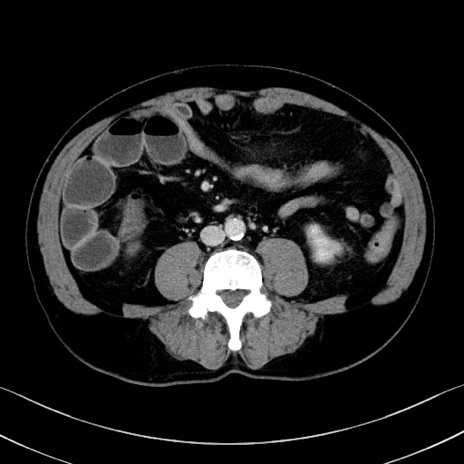

症例35(横断像)

【症例】70歳代 男性

【主訴】腹部膨満、嘔吐

【現病歴】昨日より腹部膨満感出現。本日増悪し、仙痛出現。嘔吐あり、受診。

【既往歴】糖尿病、胆摘後

【身体所見】BP 149/80mmHg、HR 74/min、BT 35.9℃、腹部:膨満、軟、圧痛なし。腸雑音減弱あり。上腹部正中切開瘢痕あり。

【データ】WBC 13500、CRP 1.72